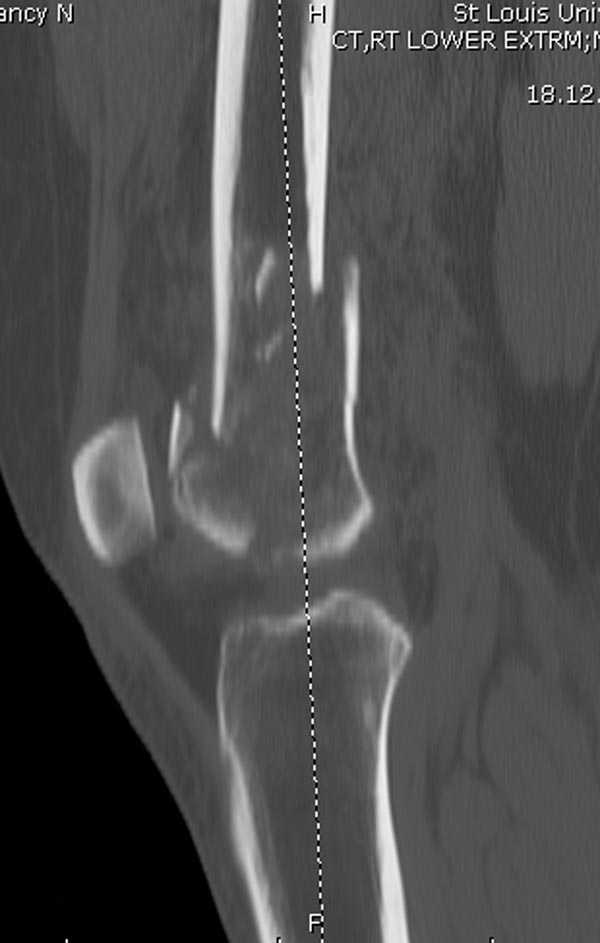

Это перелом не нижней трети, а дистального суставного конца, с распространением на диафиз. Что-то между C2 и C3. Но пока ближе к C2 по увиденному - вторую проекцию еще не показали.

На профиле стало видно, что открываться придется, это перелом C3, хотя можно назвать и C2+, т.е. с еще и фронтальным раскалыванием одного мыщелка. Надо сделать медиальную артротомию, ступеньку на внутреннем мыщелке устранить, ввести либо несколько временных спиц спереди назад, или сразу винт вдоль эллипса мыщелка. А дальше как выше написано - дистрактор, и штифтовать. Учитывая наличие открытого колена - вполне уместно ретроградно.